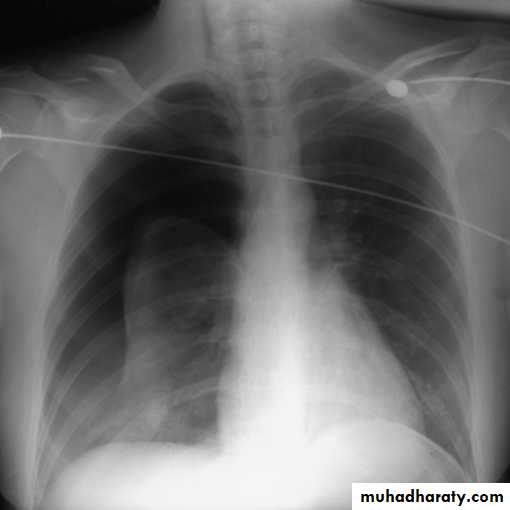

This frontal CXR reveals complete collapse ofthe right lung due to a massive right pneumothorax, which is also shiftingthe heart and other mediastinal structures to the left, (a tension pneumothorax).